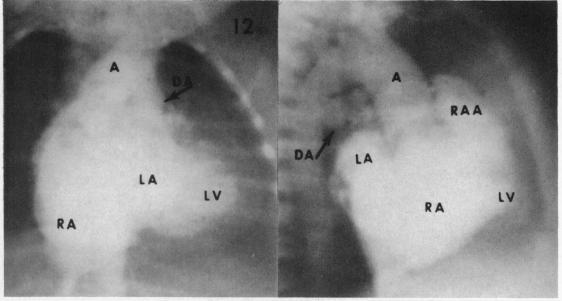

RADIOLOGICAL ASPECTS OF PULMONARY ATRESIA WITH INTACT VENTRICULAR SEPTUM.

Br Heart J. 1963 Sep;25(5):655-62. doi: 10.1136/hrt.25.5.655.